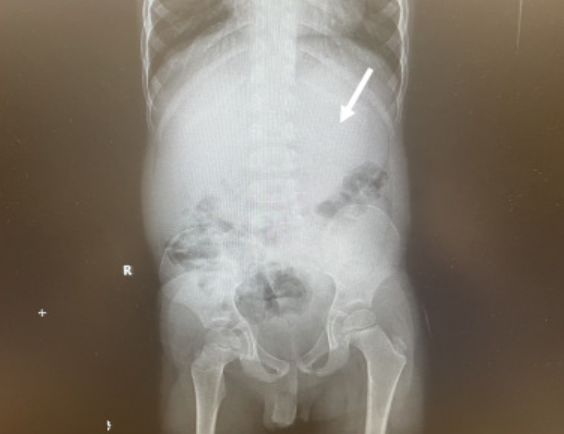

4-latek trafił do kliniki w Cleveland. Zespołem lekarzy, który opiekował się maluchem, kierowała doktor Chizite Iheonunekwu. Badanie tomografii komputerowej żołądka potwierdziło, że mały pacjent połknął na raz całe opakowanie gumy do żucia, a ta zlepiła się w wielką masę.

Połknięte przez chłopca gumy zajęły aż 25 proc. objętości jego żołądka. Na czas przeprowadzenia operacji dziecko zostało uśpione. Trzeba było kilku prób, aby kulę ostatecznie udało się usunąć z organizmu pacjenta.

Guma zajmowała aż 25 proc. objetności żołądka dziecka